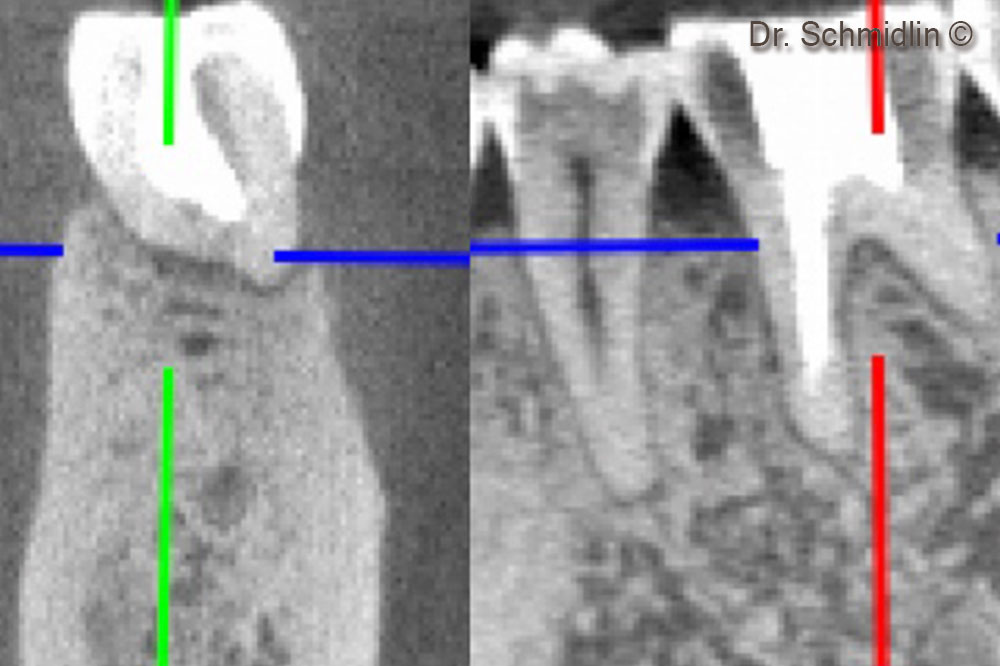

CBCT of the furcation area after 6 months

CBCT of the mesial root after 6 months